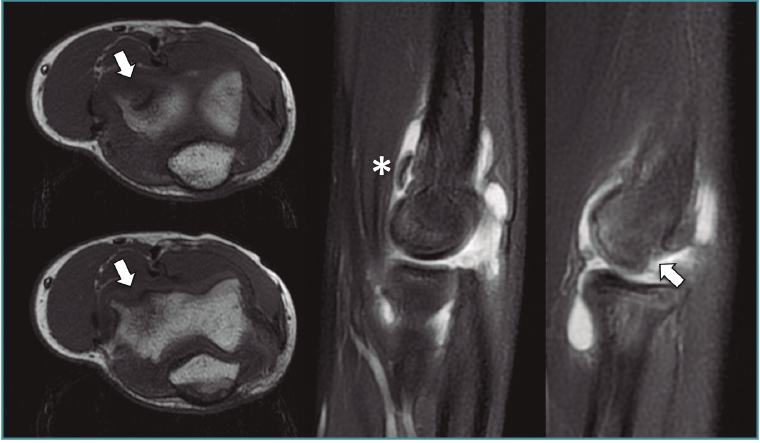

Figura 3. Imágenes de resonancia magnética de una osteocondritis disecante de codo de tipo IV de la International Cartilage Repair Society (ICRS). Se aprecia el defecto en los planos transversal y sagital en la región anteroinferior del capitellum (flechas) y cuerpo libre en la cámara anterior (asterisco).